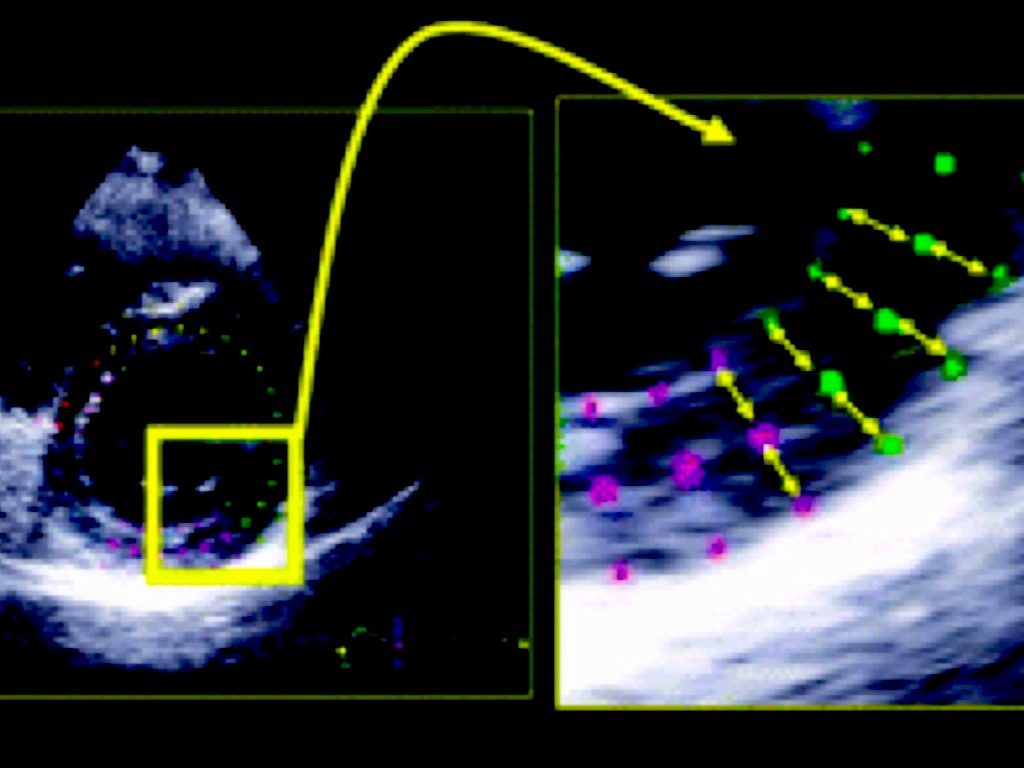

ALTERAÇÕES STRAIN LONGITUDINAL

Pacientes assintomáticos- preditor dç isquêmica estável

Lesões > 50%

Lesões > 70% = eco estresse

EAM- níveis elevados de troponina / > área isquêmica/ transmuralidade cicatricial

Terapia de reperfusao- preditor de eventos cardíacos adversos